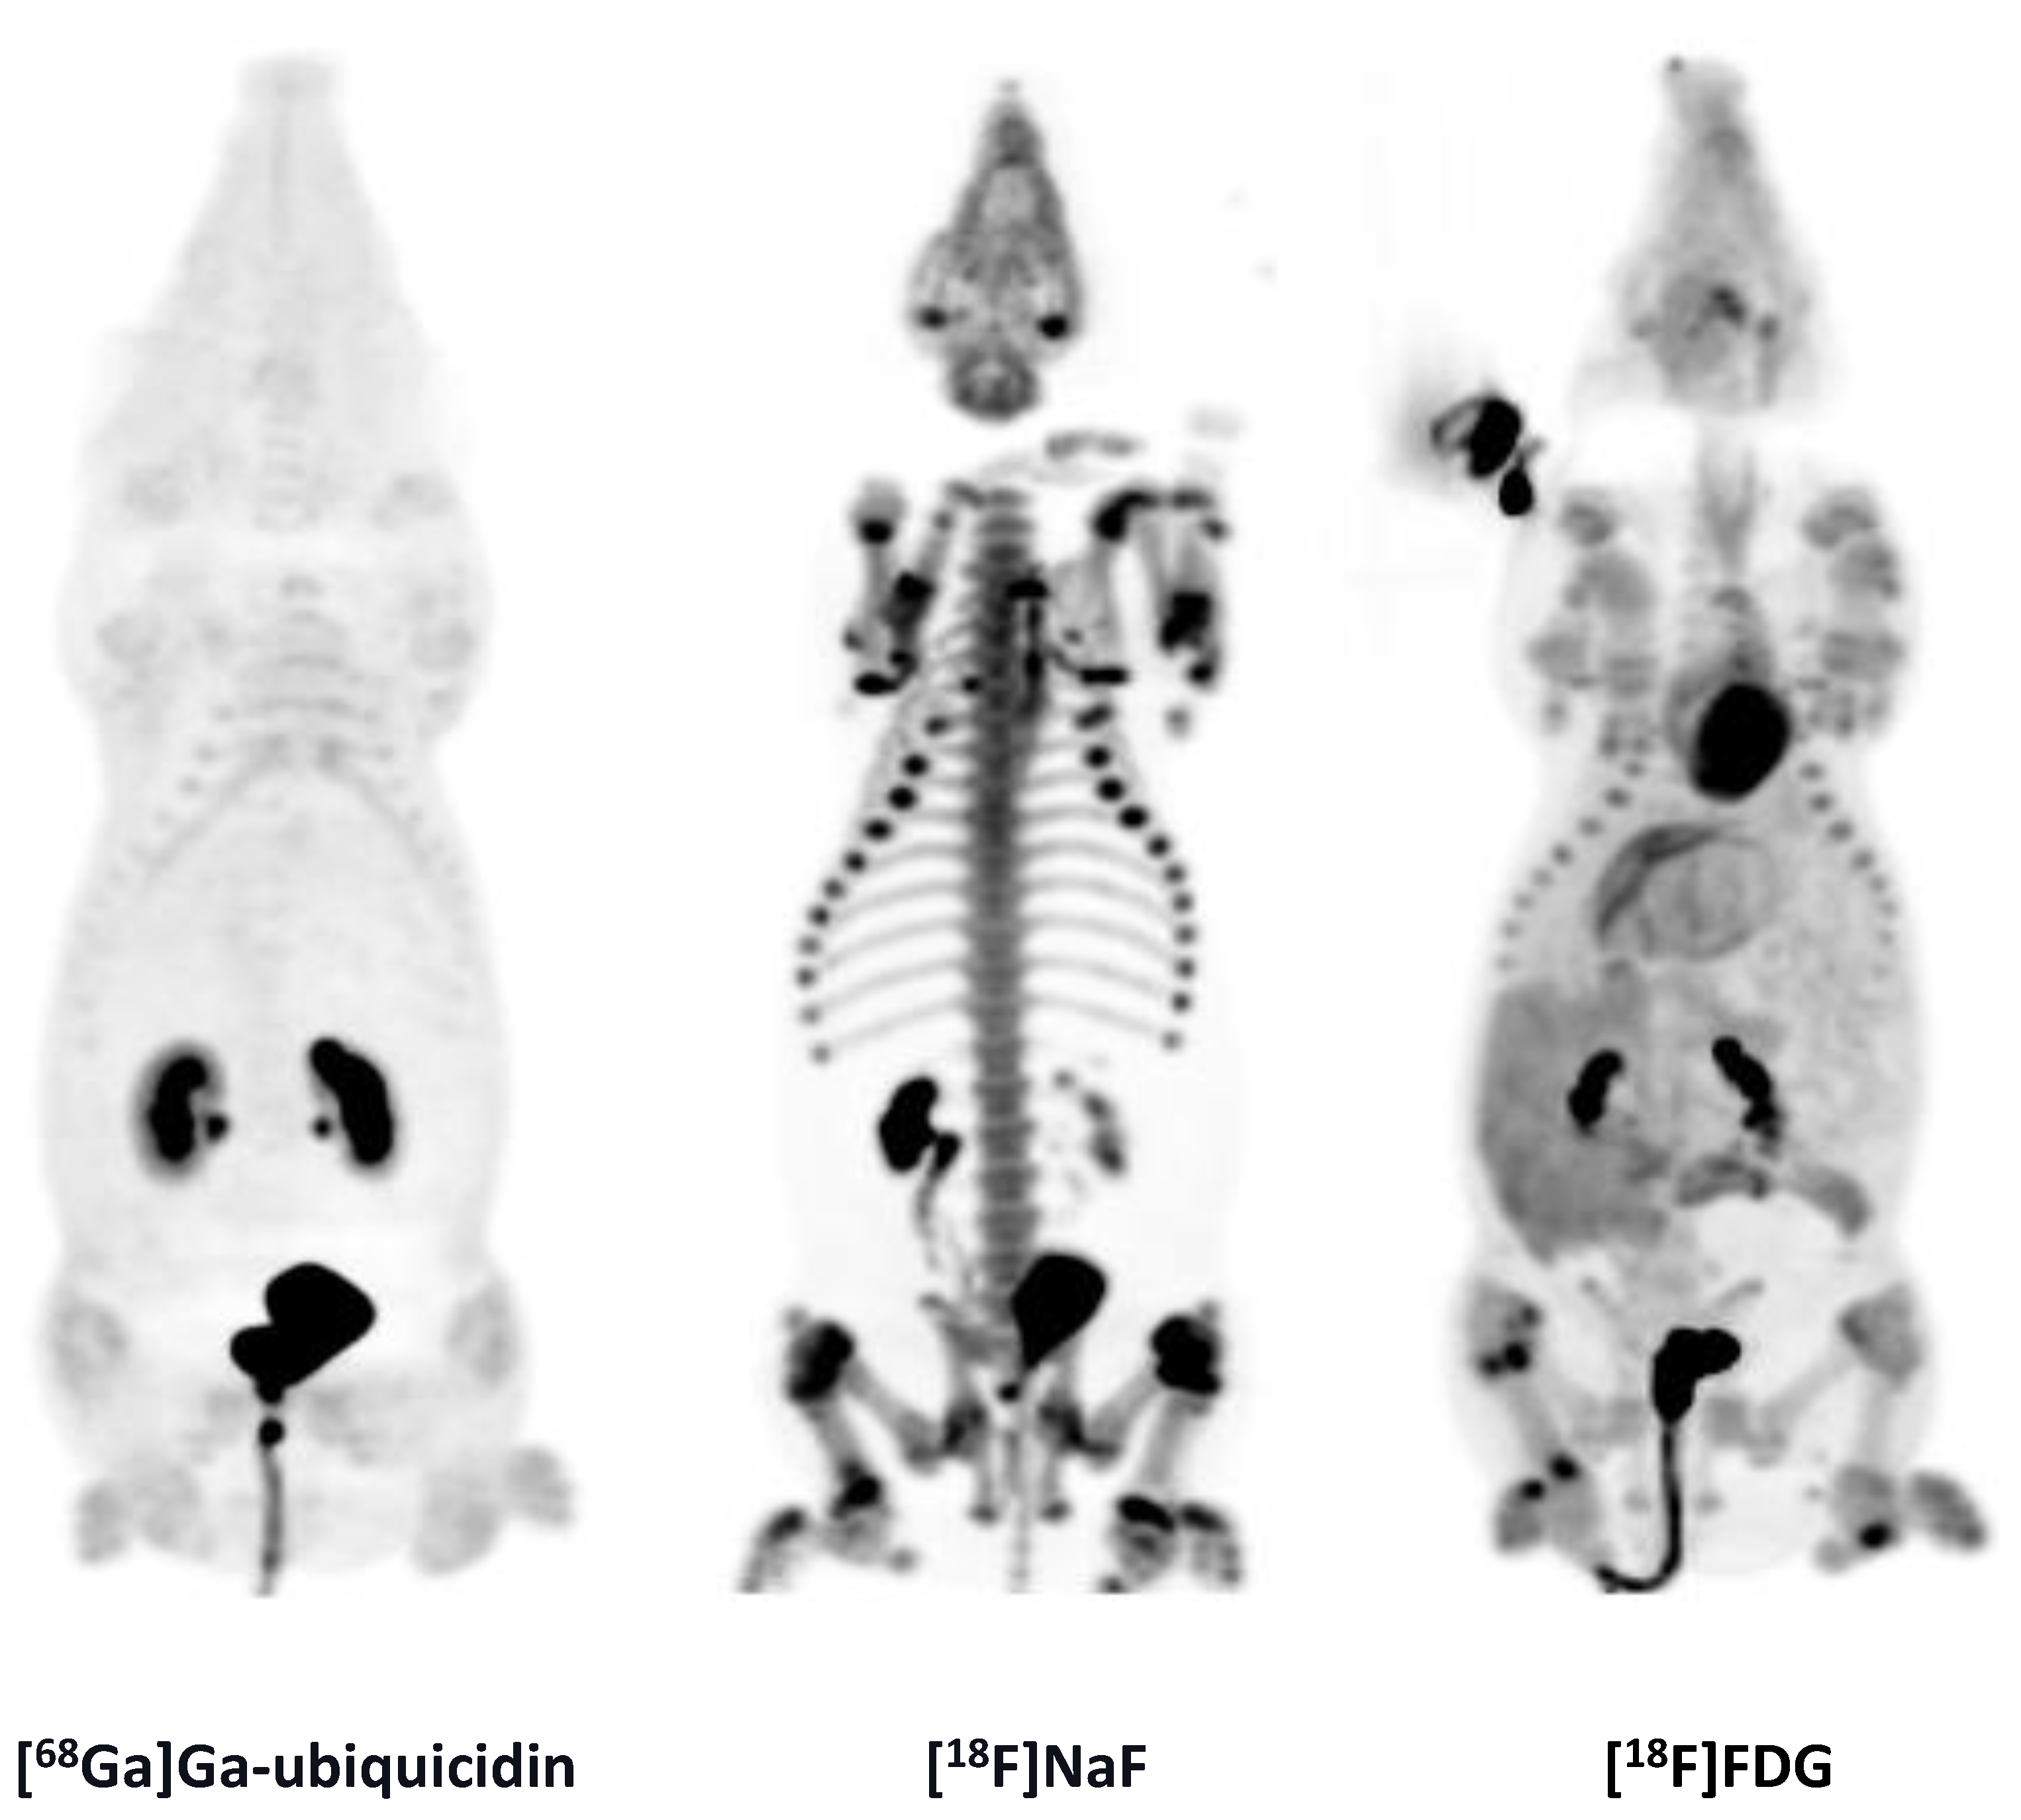

While previous evaluation in murine subcutaneous S. aureus infections showed uptake of [68Ga]Ga-DOTA-K-A9 [9,14], we saw no increased tracer activity of the two S. aureus phage displayed selected peptides, [68Ga]Ga-DOTA-K-A9 (Figure 1) and [68Ga]Ga-GSG-KA-11 (Figure 2) in 9 and 5, respectively, porcine OM lesions. Figure 3 shows the bio-distribution of the peptides in pigs. Both peptides were excreted by the liver and kidneys.

MIPs of the [18F]FDG, [68Ga]Ga-DOTA-K-A9, and [68Ga]Ga-DOTA-GSGK-A11.

MIPs of the [68Ga]Ga-ubiquicidin, [18F]NaF, and [18F]FDG distribution in pig 9.